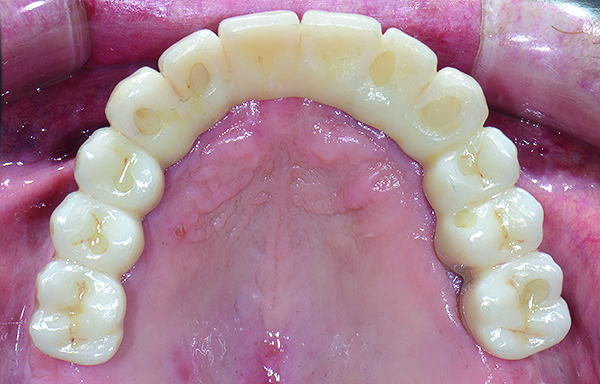

Upon completion of the above procedures, alginate impressions were made of the provisionals. Polyvinylsiloxane closed-tray transfer impressions were made of the maxillary and mandibular arches. The bite registration was obtained by transferring the provisionals to the master casts and mounted on an appropriate articulator. The provisionals and master casts were scanned into the digital environment for production of the maxillary and mandibular prototypes. The prototypes offer the advantage of being able to digitally correct minor design issues and then verifying and adjusting intraorally (Figure 7 through Figure 10).

The maxillary prototype was adjusted, polished, and left to function with the mandibular provisional. The definitive maxillary zirconia restoration was then completed from the information provided by the prototype, and the cutbacks for the facial porcelain (Nos. 6 through 11) were done after milling but before sintering. Subsequently, the mandibular prototype was adjusted to the sintered and colored maxillary zirconia framework before the application of porcelain to Nos. 6 through 11 and final glazing (Figure 11). Following this step, the mandibular definitive monolithic zirconia restoration was milled, colored, and sintered. The facial porcelain (Nos. 6 through 11) was applied, and then both maxillary and mandibular restorations were stained and glazed (Figure 12). Both bridges were inserted at the same time (Figure 13 through Figure 15). Minor occlusal adjustments and oral hygiene access was verified and the zirconia surfaces polished. The bridge screws were torqued to 20 Ncm according to the manufacturer’s recommendation, and No. 24 was luted with a provisional cement. Postoperative radiographs were taken (Figure 16).

Fig 18. Intraoral occlusal views of maxillary (Fig 18) and mandibular (Fig 19) zirconia restorations at 1.5 years.

Figure 18